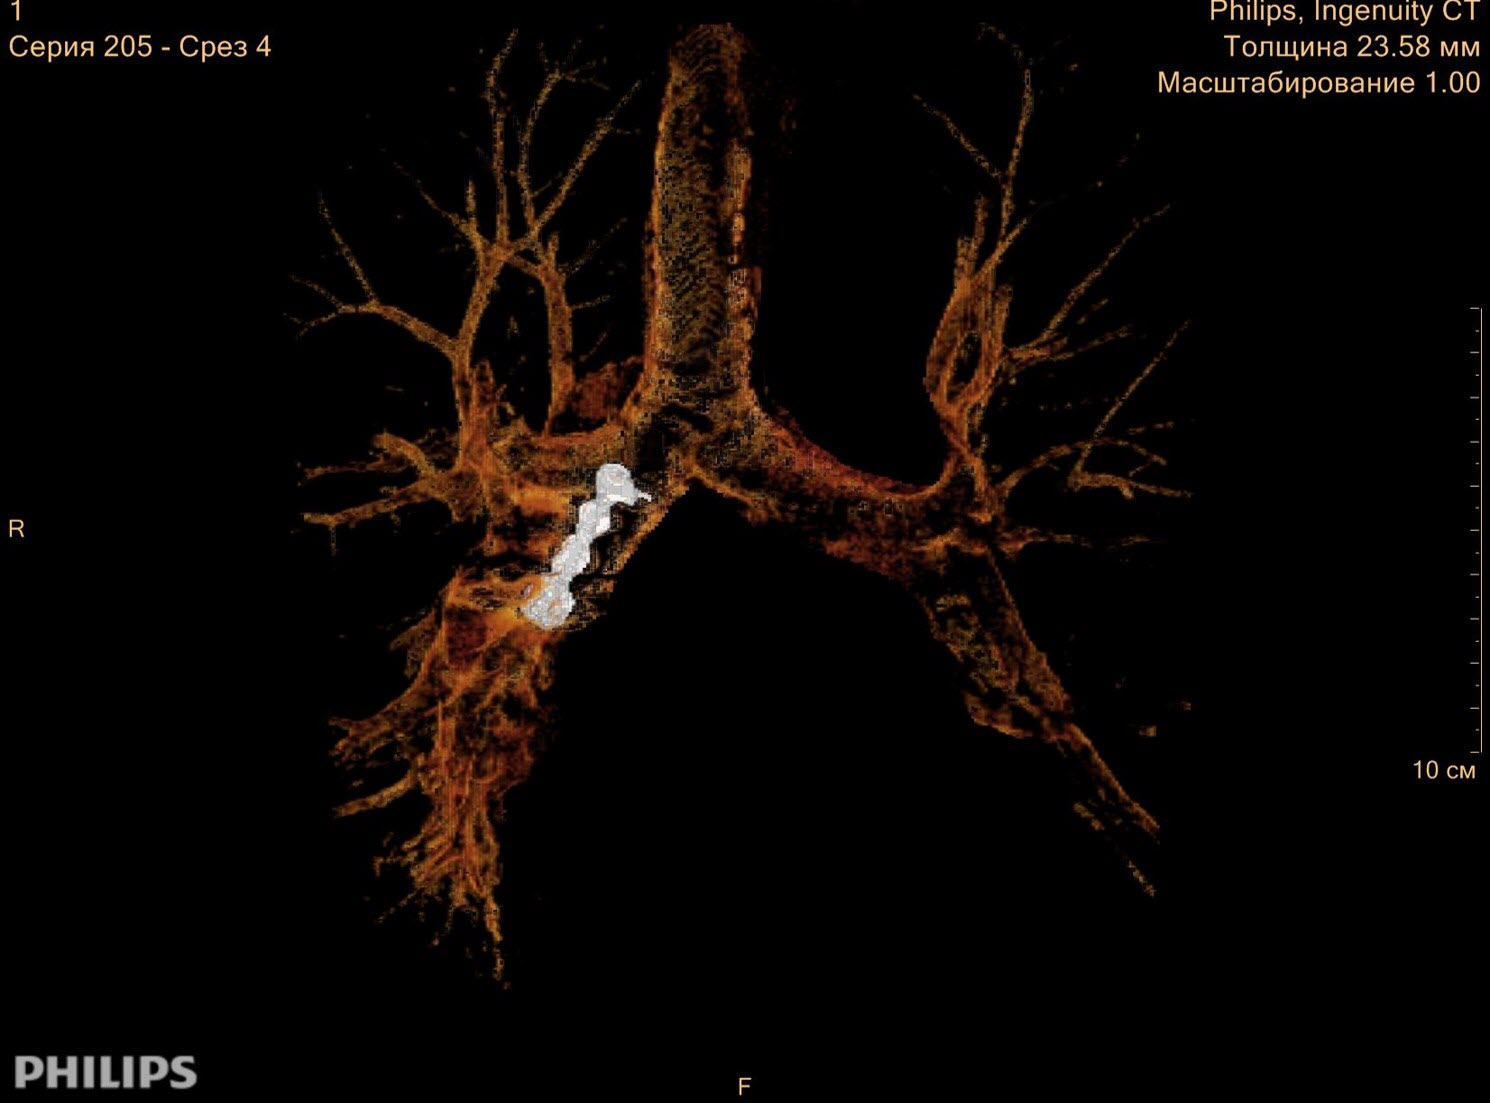

Federal Almazov North-West Medical Research Centre “Nice imaging of artificial teeth in the bronchus. With IMR we could create very demonstrative 3D model”

Russia

Dr. Gleb & Team